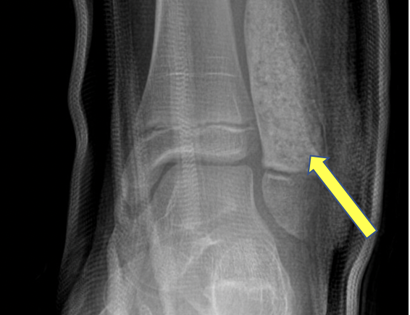

The empty bone cavity is usually filled with bone graft or bone cement. Bone can be donated (allograft) or taken from the patient themselves (autograft). Fixation devices, such as a plate and screws, may be used in specific situations to prevent postoperative fracture. This example of an X-ray shows the bone graft filled in nicely. It looks particulate. In this case, the patient was placed in a cast to protect from fracture and allow the graft to heal.